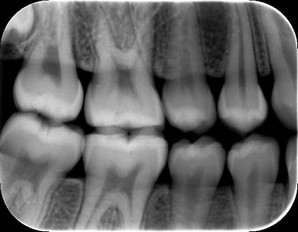

Hình ảnh của phim cắn cánh (bitewing)

Kết quả cho thấy rằng so với nhóm đối chứng, người tham gia khảo sát với u màng não có nhiều khả năng họ đã từng chụp X-quang cắn cánh (bitewing x-quang). Đây là loại kiểm tra thấy được từng cặp thân răng của hàm trên và dưới cùng một lúc.

Những người tham gia trong cuộc khảo sát đã chụp X-quang định kỳ hàng năm hoặc thường xuyên hơn, thì khả năng phát triển một khối u màng não cao hơn từ 1,4 đến 1,9 lần so với nhóm đối chứng.